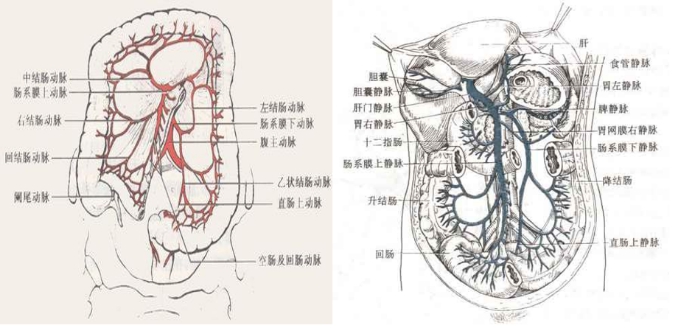

3 肠系膜循环系统的解剖及生理学特点小肠主要靠肠系膜上动脉(superior mesenteric artery, SMA)供血,另外还有部分发自腹腔动脉系统的侧支循环,通过胰十二指肠上、下动脉以及肠系膜下动脉供血(图 1)。肠内血液通过门静脉回流。其内脏血液循环占心输出量的15%~35%(主要取决于进食状态);但氧气摄取量却相对较低,这主要与门静脉对肝脏的血液供应有关。一般而言,小肠血供须减少50%以上才会出现缺血表现[7]。

| 图 1 肠系膜动静脉血供示意图 |